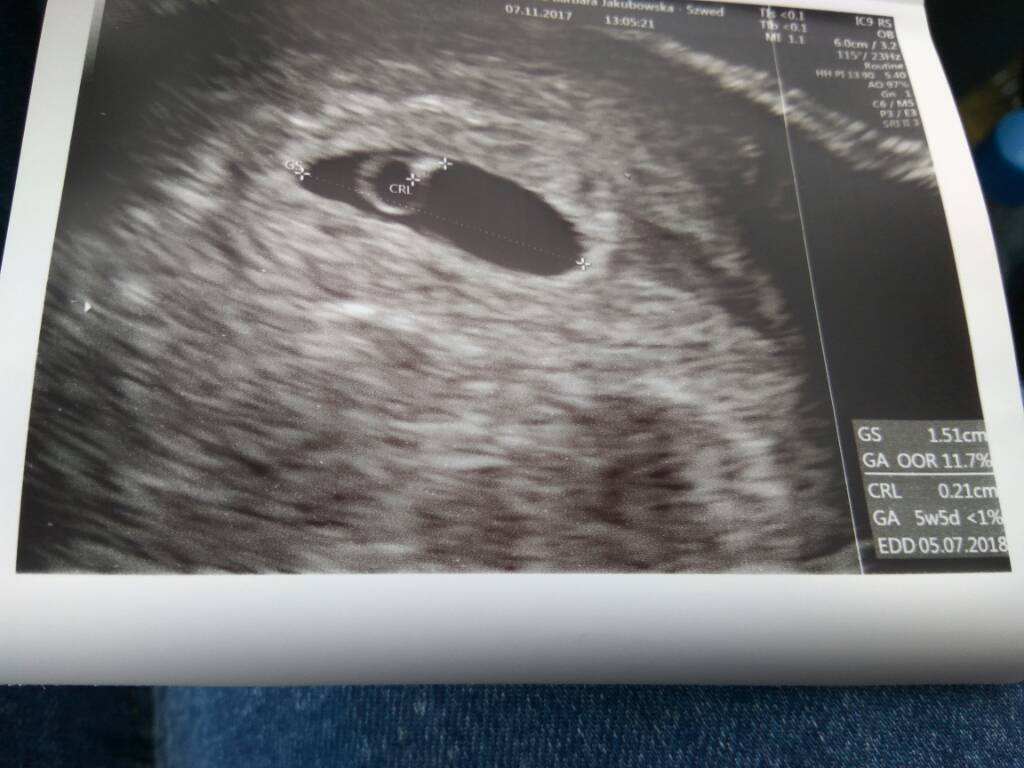

Ja dziś po pierwsze j wizycie. Z USG maluszek mniejszy więc termin na lipiec ;) mialam pozna owulację. Moje zdjęcie z dzisiejszej wizyty;)

1510065888-d4b7700361996f0b-aaaaaa.jpeg